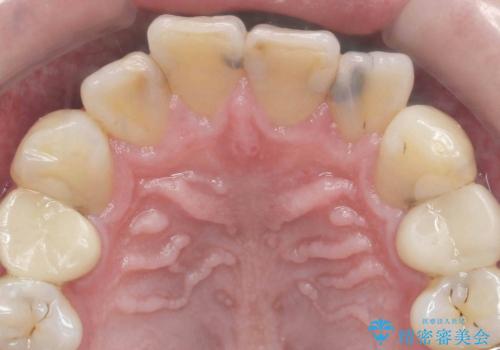

- 前歯の黒い影が大きくなってきている、と虫歯の治療を希望され来院されました。

視診、X線写真より前歯に発生した大きな虫歯が認められました。

虫歯の丁寧な除去後、今後の虫歯の2次的な発生を防ぐべく、相談の上コンポジットレジン修復ではなくジルコニアクラウンによる治療を行っていくこととしました。